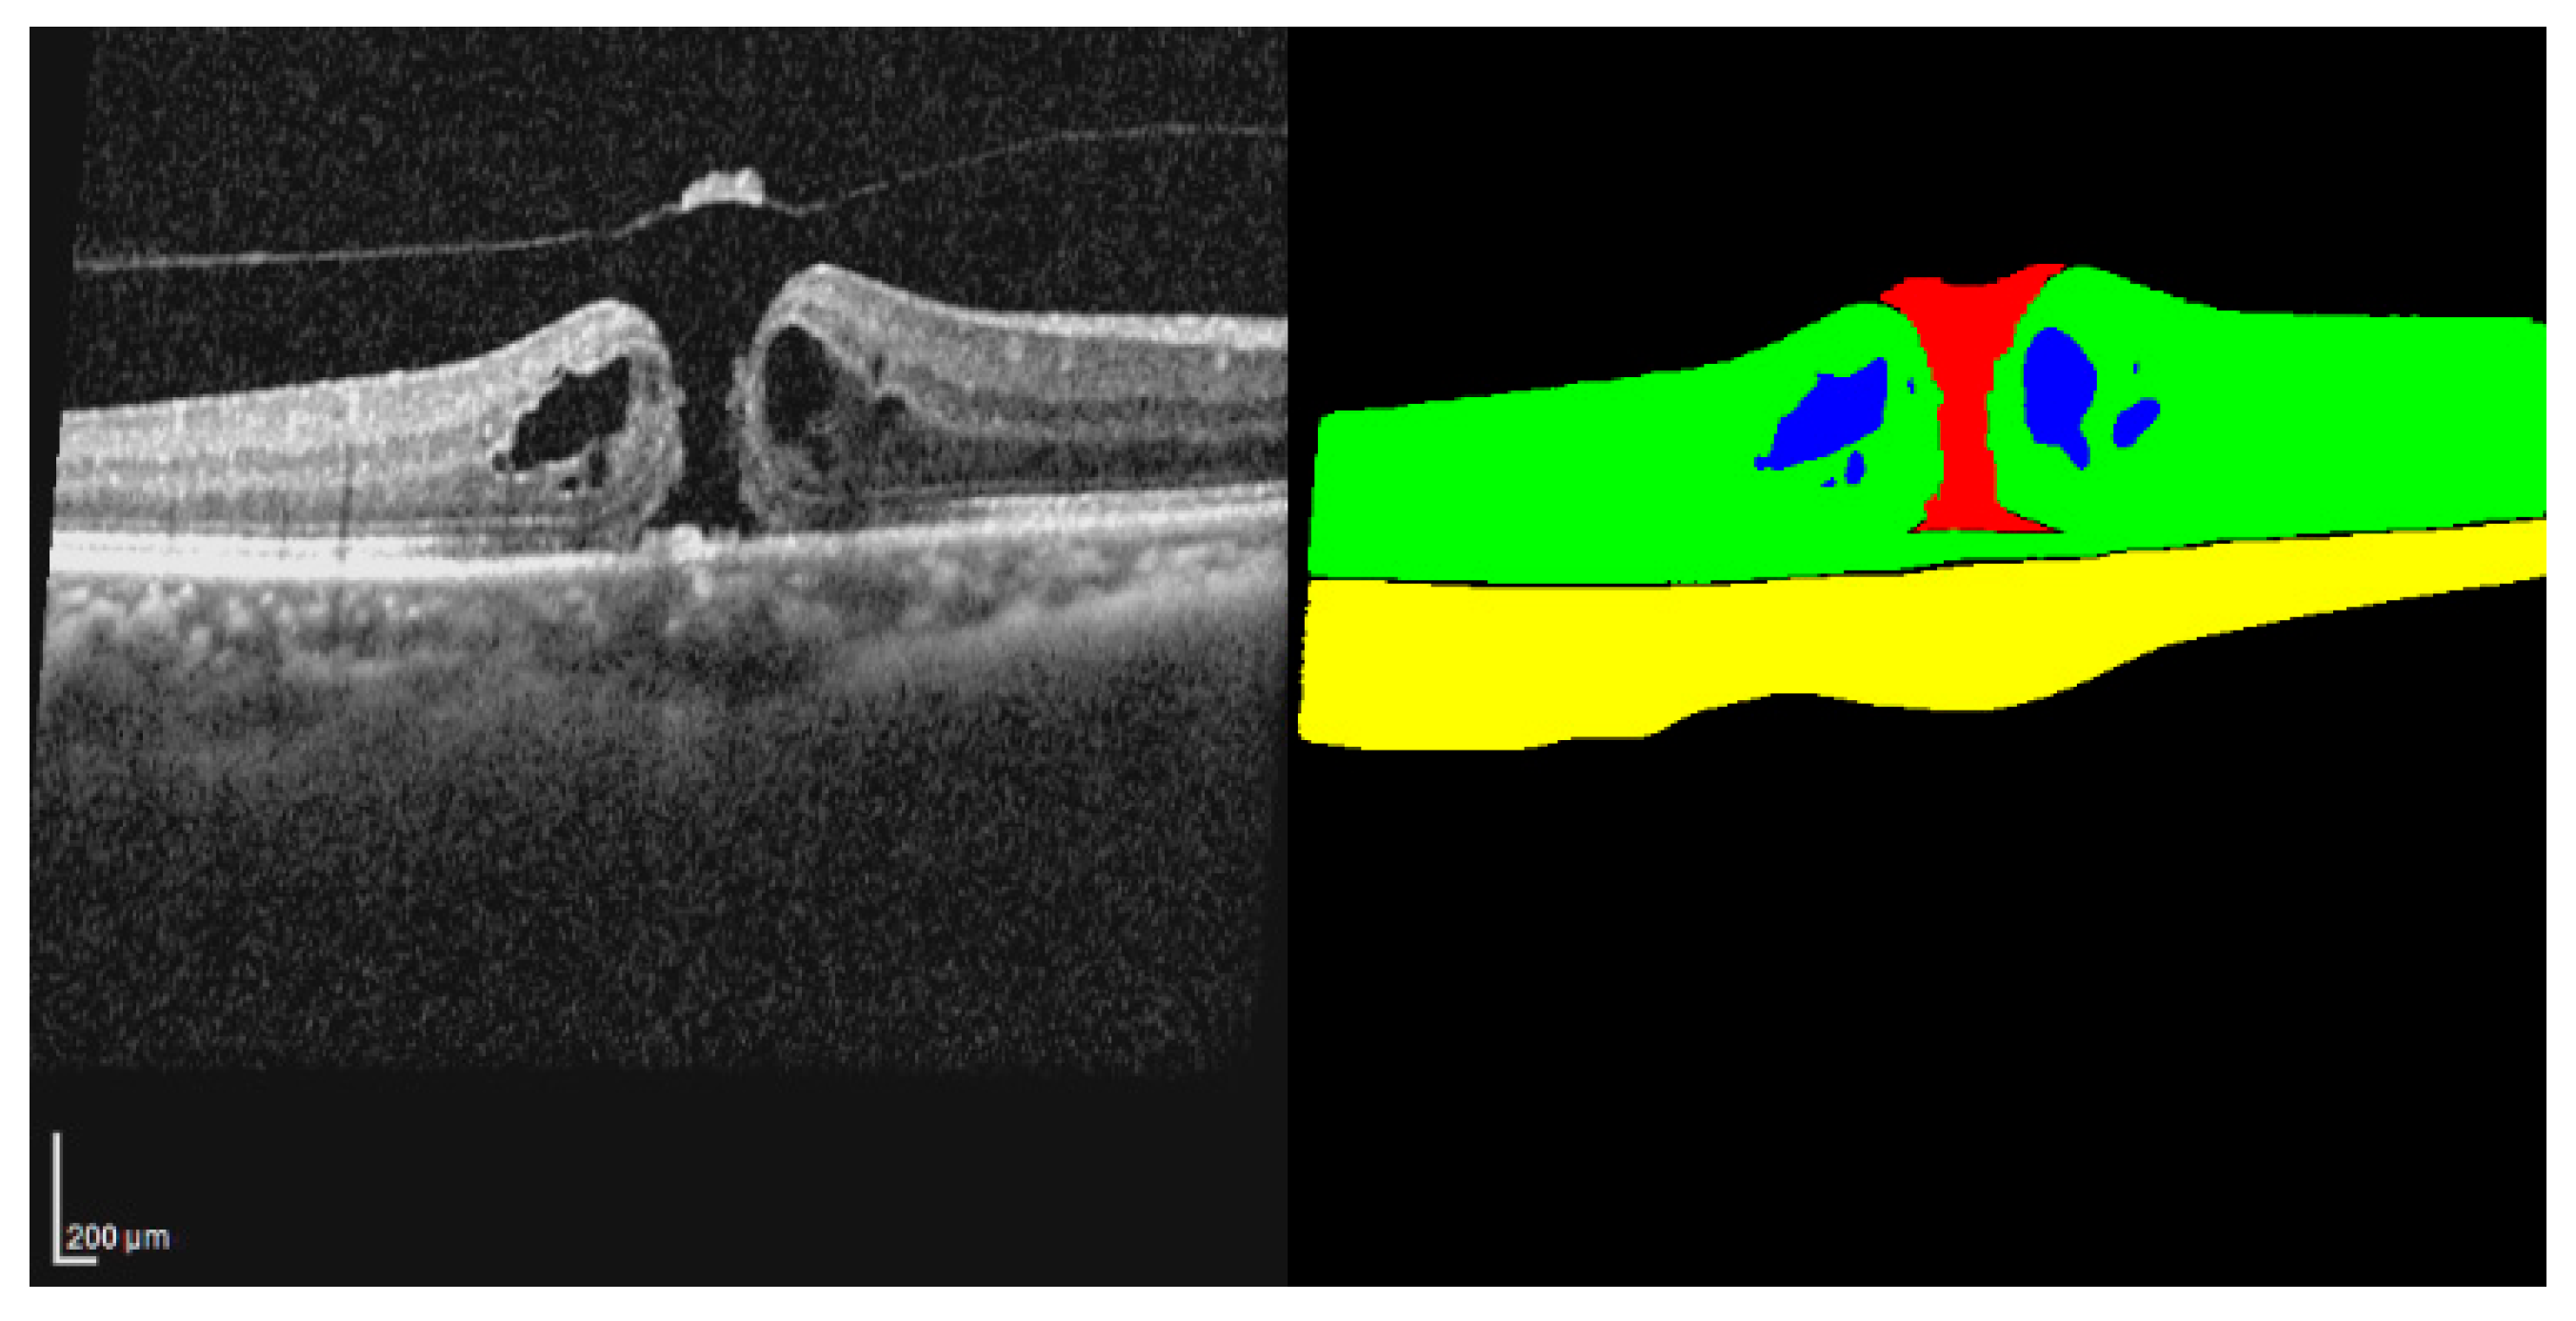

This study used the open-access OIMHS dataset [15,16]. Since the OIMHS data are anonymized and publicly available, no additional ethical approval was required. Data collection was conducted with approval from Zhejiang Provincial People’s Hospital (QT2023024) [16]. The dataset contains OCT B-scans of full-thickness macular hole (FTMH) cases and corresponding segmentation masks for each slice. The masks are labeled with four classes: retina, macular hole, intraretinal cyst, and choroid. Thus, each raw OCT slice is paired with a mask image of the same size and resolution. In addition to the OCT B-scans, the dataset also contains information on image-quality and participant demographics. In our study, these masks were directly used for training, testing, and evaluation. An image–mask pair from the dataset is presented in Figure 1.

Figure 1. An example OCT–mask pair from the dataset. The raw OCT image is shown on the left, and the corresponding mask is shown on the right. The mask shows hole in red, cyst in blue, retina in green, choroid in yellow, and background in black.